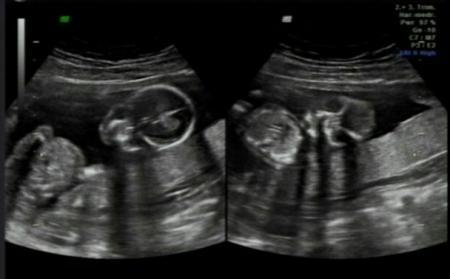

Ja hab ein Bildchen bekommen, aber daran sieht man schon das unser Krümel garkeine Lust hatte sich zu zeigen , vielleicht ist es beim nächsten Termin etwas aufgeschlossener :)

Bild zu